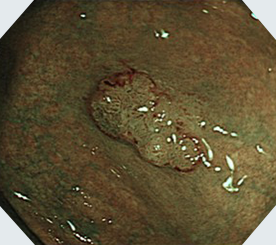

NBI+拡大観察

クリスタルバイオレット+拡大観察ハイビジョン対応の高画質で、拡大観察できる光学ズーム機能を搭載。NBIとの併用により、腫瘍などの詳細な観察・診断が可能です。

粘膜の表面だけを可視化する波長に切り替えて、病変の拡大観察を行うことで良悪性を判断できます。病理検査を行い、診断を確定できます。